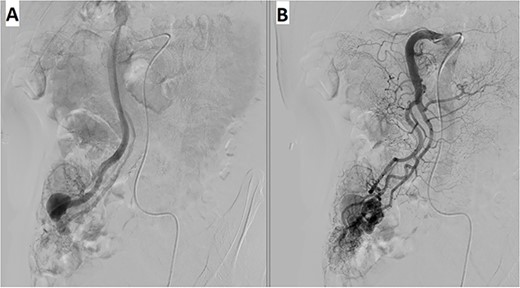

A 57-year-old male patient with a history of hypertension was referred to our hospital for multiple episodes of painless bloody stools for 2 weeks. No gastrointestinal symptoms were observed, such as abdominal pain, nausea or vomiting. A digital rectal examination showed bright red blood. On admission, laboratory evaluation revealed mild anemia with hemoglobin of 103 g/dL. Other than that, there were no other abnormalities. Lower and upper gastrointestinal endoscopy was performed, but the cause of the bleeding could not be identified. Due to the signs and symptoms of ongoing bleeding, we decided to perform imaging tests to make a diagnosis. Abdominal contrast-enhanced computed tomography (CT) revealed a thickened appendix (17 mm in diameter and wall thickening 6.4 mm) without signs of inflammation and images of vascular proliferation and dilated vein around the appendix (Fig. 1). An angiography was performed and demonstrated the AVM of the appendicular artery and vein (Fig. 2).

Angiography revealed (A) vascular tangle with (B) early venous filling in the appendicular artery and vein.